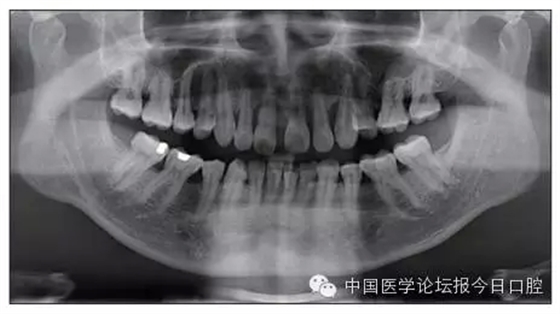

本病例為慢性牙周炎致前牙漂移、深覆(牙合)患者。本病例采用無托槽隱形矯治技術(shù)進行治療。無托槽隱形矯治器具有可摘戴、便于口腔衛(wèi)生維護和牙周治療的優(yōu)點,更適合于伴有牙周炎的錯(牙合)畸形患者的治療。 患者男,48歲,前牙有縫、前突求診。 患者面部對稱,側(cè)面觀上頜前突,下頜后縮。 口內(nèi)情況:恒牙列,24、34、44缺失,磨牙Ⅲ類關(guān)系,上牙列散隙,上前牙扇形漂移。前牙深覆(牙合)、深覆蓋??谇恍l(wèi)生較差,11與12間牙齦乳頭紅腫,多個牙探診有牙周袋形成,11松動Ⅰ度,余切牙松動(-),患者面像及口內(nèi)像如圖1、2所示。 圖1 治療前面像 圖2 治療前口內(nèi)像 全口曲面體層片(圖3)顯示,患者全牙列牙槽骨吸收;根尖片(圖4)示11近中牙槽骨角形吸收已達根尖1/3,21牙槽骨嵴頂吸收至根1/2,23牙槽骨近中骨板角形吸收至根1/2。磨牙區(qū)骨嵴頂吸收3mm。治療前頭顱側(cè)位片見圖3,治療前ODS模型見圖5。 圖4 治療前根尖片 圖5 治療前ODS模型 牙型:安氏Ⅲ類。骨型:Ⅱ類。面型:上頜前突,下頜后縮。 問題列表為:①上牙列間隙;②上切牙病理性牙移位;③前牙深覆(牙合)、深覆蓋;④24、34、44缺失;⑤慢性牙周炎。 矯治目標包括:①排齊牙列,關(guān)閉牙列間隙;②改善前牙深覆(牙合)、深覆蓋;③改善牙周狀況。 矯治設(shè)計有:①牙周基礎(chǔ)治療與維護。②壓低、內(nèi)收上切牙,關(guān)閉上牙列間隙。③壓低下切牙,伸長下后牙,整平Spee曲線,改善前牙覆(牙合)、覆蓋。 患者進行全口齦上潔治、齦下刮治,口腔衛(wèi)生宣教,并按牙周醫(yī)師的要求,每2~3個月行牙周檢查與治療。 牙周基礎(chǔ)治療結(jié)束3個月,開始隱形矯治。于14、25、35、36、45、46上粘接附件(圖6),于16、26(牙合)面粘接(牙合)墊。 圖6 ODS設(shè)計附件粘接圖示 矯治過程中注意(牙合)墊是否脫落或磨損,及時修補。 注意上前牙內(nèi)收時有無咬合干擾,及時調(diào)(牙合)。下頜前磨牙伸長到位后,磨除16、26(牙合)墊。 下頜佩戴第24步矯治器時,分別在36、37、46、47的頰、舌側(cè)粘接舌扣,矯治器上預(yù)留伸長空間,用3/16英寸、3.5盎司皮圈牽引,輔助伸長下磨牙(圖7)。 患者共戴用矯治器上頜32步,下頜26步。 矯治后,牙列間隙關(guān)閉,面型及覆(牙合)覆蓋改善。11根尖片(圖8)顯示,治療后較治療前,牙周支持組織增加,牙槽骨角形吸收區(qū)水平向縮小0.3mm,垂直向縮小0.6mm。11松動Ⅰ度,余切牙無松動。 圖8 治療后根尖片 圖9 治療后口內(nèi)像 圖10 治療后X線檢查 圖11 治療后ODS模型 正畸-牙周聯(lián)合治療對于牙周組織的影響 多學(xué)科綜合治療牙周炎患者不再是正畸治療的禁忌證。良好的牙周治療為正畸治療中的牙齒移動打下堅實基礎(chǔ),而正畸治療排齊牙齒、去除(牙合)干擾,有利于牙周健康。 牙周炎患者的正畸治療必須在牙周炎癥得到控制后才能進行,否則,菌斑會隨著牙齒的移動,特別是壓低而使牙周炎癥加重。牙周炎的正確診斷、牙周炎癥控制、正畸治療中和治療后的認真維護是治療成功的關(guān)鍵。根據(jù)臨床需要,一般每2~4周做一次潔治,每3個月進行牙周評估,同時患者必須進行非常良好的日??谇恍l(wèi)生維護。 固定矯治器使得牙周檢查、潔治和日??谇恍l(wèi)生維護變得困難,隱形矯治器可自行摘戴,便于患者日常維護和牙周治療,節(jié)約時間,提高菌斑控制效果。 有臨床研究表明,對于存在(牙合)創(chuàng)傷,伴有角形吸收的患牙,經(jīng)過牙周翻瓣手術(shù)控制住牙周炎癥后,使用正畸輕力壓低患牙,可以改善牙槽骨吸收的程度,并獲得一定程度的牙周新附著。本病例切牙壓低后,原來的牙槽骨吸收有改善。 病理性牙移位 病理性牙移位(PTM)在重度牙周炎患者中的發(fā)生率為30%~50%,且常見于上前牙區(qū)。其主要由于牙周支持組織喪失尤其是骨組織的丟失,咬合因素(如后牙缺失、前牙深覆牙合、牙合創(chuàng)傷等),頰舌唇肌力量不平衡及牙周和根尖周組織炎癥所致,是牙周炎患者要求正畸治療的主要原因之一。 PTM須通過正畸、牙周聯(lián)合,有時須配合修復(fù)才能達到理想的治療效果。正畸治療通常是壓低牙齒,臨床研究表明,牙周手術(shù)配合正畸壓低可以產(chǎn)生新附著,有利于PTM牙周組織的恢復(fù)。 本病例右上中切牙牙槽骨角形吸收,在盡量保證治療前后根尖片投照角度一致的情況下,以鄰牙作為校準,在根尖片上對治療前后的骨量進行評價,治療后牙槽骨角形吸收區(qū)水平向縮小0.3 mm,垂直向縮小0.6mm。盡管根尖片并不能說明骨量改變,但從影像學(xué)上能看到骨吸收區(qū)域有所減小。 無托槽隱形矯治器矯治牙周病的優(yōu)勢 無托槽隱形矯治器具有可摘戴、便于口腔衛(wèi)生維護和牙周治療的優(yōu)點,更適合于伴有牙周炎的錯(牙合)患者的治療;同時,無托槽隱形矯治器佩戴后具有牙弓夾板和(牙合)板的作用,可有效減少側(cè)向力,有利于牙周的恢復(fù)和減輕牙齒松動;由于無托槽隱形矯治器的設(shè)計是在三維數(shù)字模型上進行的,每個矯治器移動牙齒的數(shù)量和每個牙齒的移動距離可以得到量化控制,因而可以根據(jù)患者牙槽骨水平和對矯治力的耐受情況個性化設(shè)計矯治力,并且可以根據(jù)矯治中牙齒移動情況調(diào)整后續(xù)矯治器的設(shè)計。 有關(guān)磨牙伸長 單純使用無托槽隱形矯治器同步伸長后牙比較困難。該病例先使用磨牙(牙合)墊打開咬合,通過矯治器伸長前磨牙,在前磨牙建立咬合后,磨除磨牙上的(牙合)墊,通過輔助牽引伸長磨牙,最終達到伸長后牙、整平Spee曲線的目的。 史真,主任醫(yī)師,現(xiàn)任北京黃寺整形外科醫(yī)院口腔科主任,第四軍醫(yī)大學(xué)口腔正畸學(xué)碩士,為世界正畸醫(yī)師聯(lián)盟(WFO)會員、全軍口腔醫(yī)學(xué)專業(yè)委員會委員、中華口腔正畸專業(yè)委員會委員、中華醫(yī)學(xué)美學(xué)與美容學(xué)會齒科美容學(xué)組成員、北京口腔醫(yī)學(xué)會兒童口腔專業(yè)委員會常務(wù)委員、北京口腔醫(yī)學(xué)會正畸專業(yè)委員會委員、《中華醫(yī)學(xué)美學(xué)與美容》雜志審稿專家,是我國最早開展無托槽隱形矯治技術(shù)的口腔醫(yī)師之一。

圖3 治療前頭顱側(cè)位片及曲面體層片